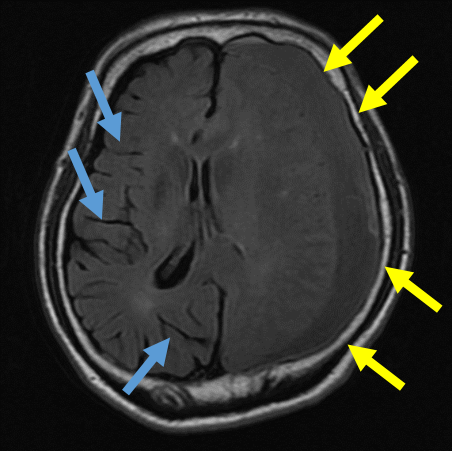

慢性硬膜下血腫の典型的な画像

頭痛を主訴とした若い患者さんの慢性硬膜下血腫の例

高齢者と異なり、頭痛が主要な症状として現れることがあります。この画像では、頭蓋骨の内側に少量の血腫が確認できます。

一カ月前に転倒し頭部打撲。転倒当日CT検査を行い異常なし。転倒から一カ月後から返答がうわのそら、さらに歩行時のふらつきが目立つようになり受診

→に血腫を認める。血腫による圧迫により健常側に見られる脳のしわ(→)が潰れている。

→に厚い血腫を認める